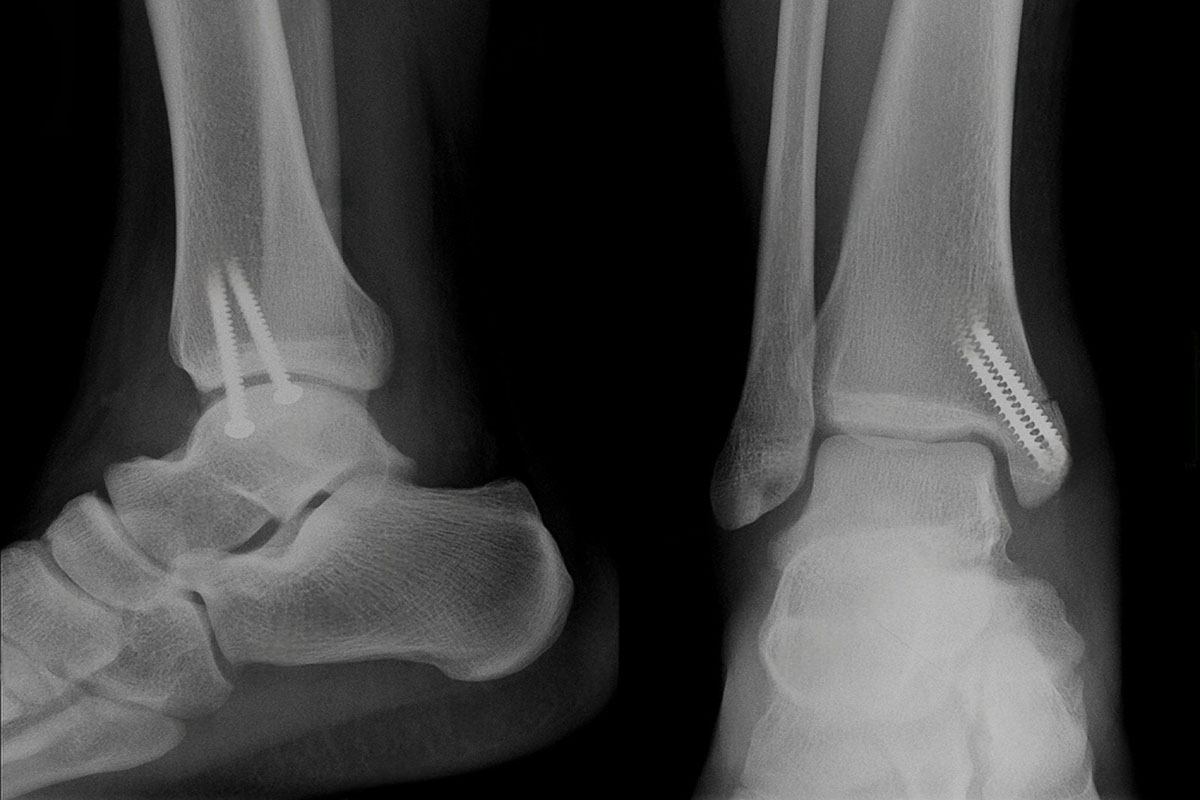

Weight-bearing foot and ankle X-rays for alignment planning in Delhi

• Weight‑bearing X‑rays: AP/lateral/oblique, hindfoot alignment view; hallux angles; Meary’s angle; talar uncoverage.

We line up your symptoms with imaging so treatment targets the true pain generator.

Hindfoot alignment view and deformity assessment in Delhi